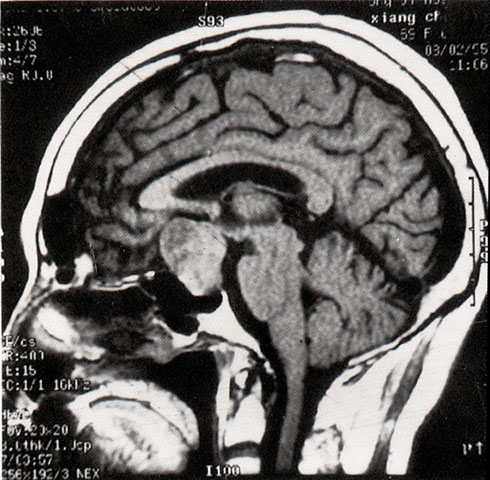

FH1061 脑垂体瘤(MRI)

光盘检索编码 FH1061  函授作业图编号 1061

图  名 脑垂体瘤(MRI)

导  学 与图1061、1062、1063、1064、1065为同一患者

讨 论 题 阅图分析